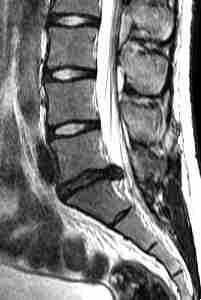

МРТ поясничного отдела позвоночника. Сагиттальная Т2-взвешенная МРТ. Грыжа диска.

Отрыв части грыжи от материнского диска приводит к образованию секвестра (оторванного кусочка). Секвестр обычно образуется при разрыве задней продольной связки, что видно при МРТ позвоночника в сагиттальной плоскости. Секвестр может смещаться вверх, вниз и немного вбок.

МРТ поясничного отдела позвоночника. Сагиттальная Т2-взвешенная МРТ. Секвестрировавшаяся грыжа диска.